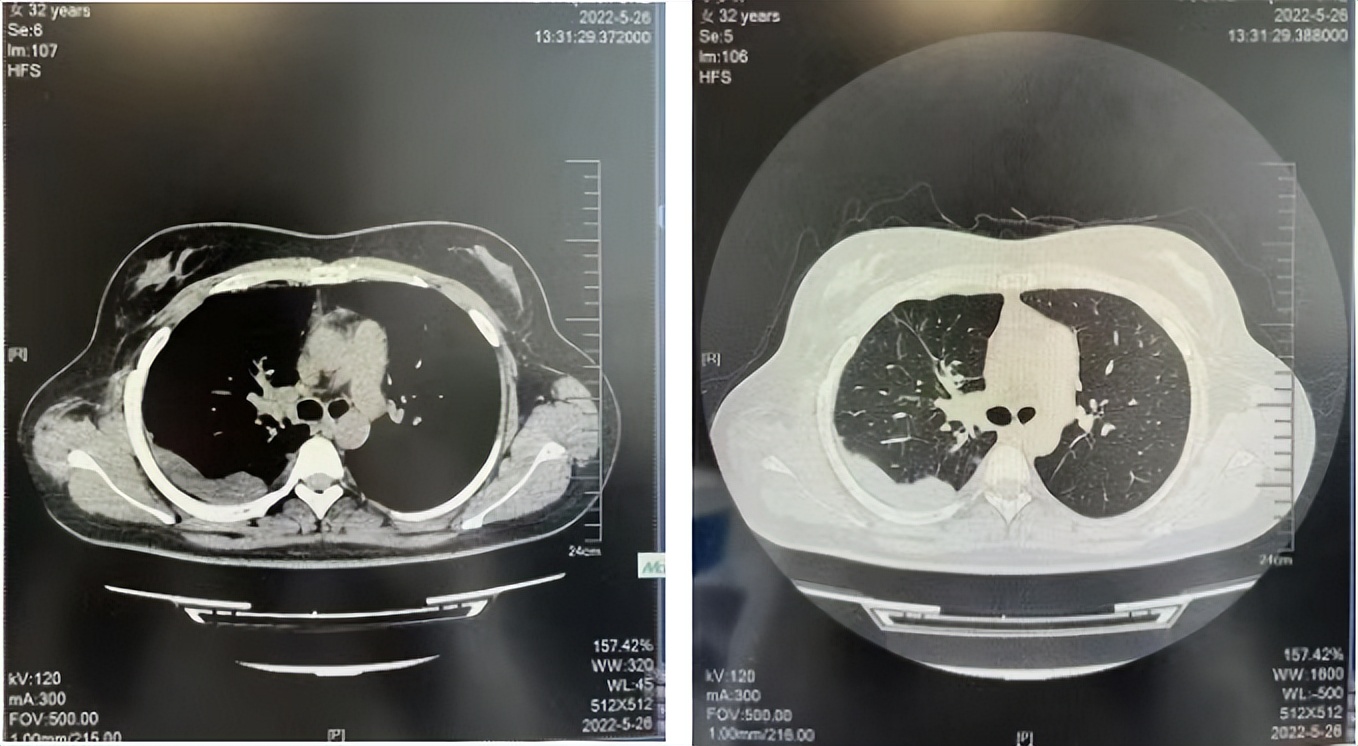

2016年1月复查CT提示支气管截断可见新发小结节,一线治疗采用培美曲塞+DDP方案化疗4周期(培美曲塞3.36,DDP 480mg)。化疗后复查胸部CT:右肺见不规则结节样影,最大层面大小约19mm*8mm,较前比较明显增大,疗效评估PD。2017.3-2017.4予单药多西他赛化疗3周期,疗效评估SD。2018年5月末复查CT提示结节较前增大,评效为PD,2018年6-10月予多西他赛+CBP化疗4周期,疗效评估SD。2022年5月患者出现活动后气短,复查胸部CT示右肺膨胀不良;右侧胸腔积液增多。胸腔积液包埋病理示符合肺腺癌细胞。行NGS基因检测:EML4:exon13-ALK:exon20融合。PD-L1(克隆号22C3)TPS<1%。

临床诊断:右肺上叶恶性肿瘤rT0N0M1a IVA期(第9版分期);恶性胸腔积液。

诊疗经过:2022年5月始口服克唑替尼3个月,出现肝功能异常(DILI 2级伴临床症状),改用恩沙替尼靶向治疗至今,目前评效为维持PR。恩沙替尼应用期间出现轻度肝功能异常(DILI 1级),对症处理后好转。截止目前PFS 33个月。